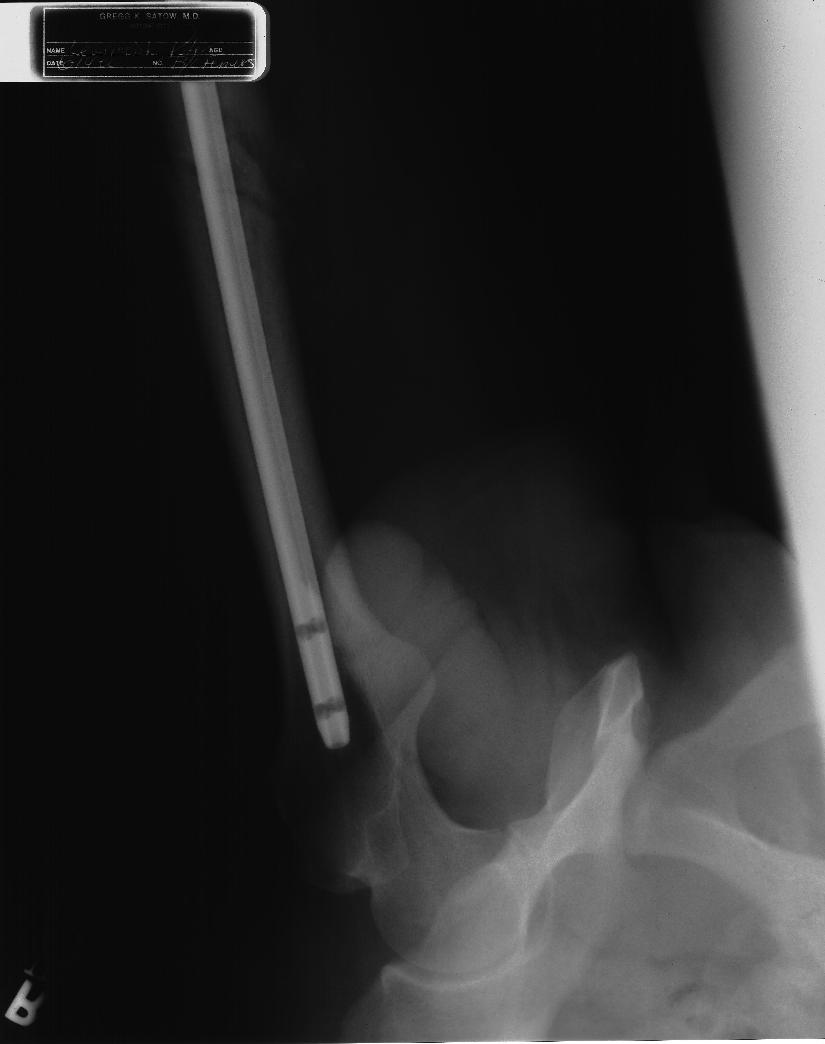

TitaniumLegs 8 #138 July 1, 2003 QuoteDude, you arent going with the shrinkage excuse are you??? OK, I confess. It's just like a penis only smaller! (©Chris DeBar) I'm not very good in bed, but at least it's over quickly. QuoteCome on show the side view.... Its all there in black and white. Show your penis!!! Noone else has had the balls. You asked for it... Edit: Now none of the girls are going to get any sleep tonight. (Come to think of it, neither will some of the boys!!) (>o|-< If you don't believe me, ask me. Quote Share this post Link to post Share on other sites